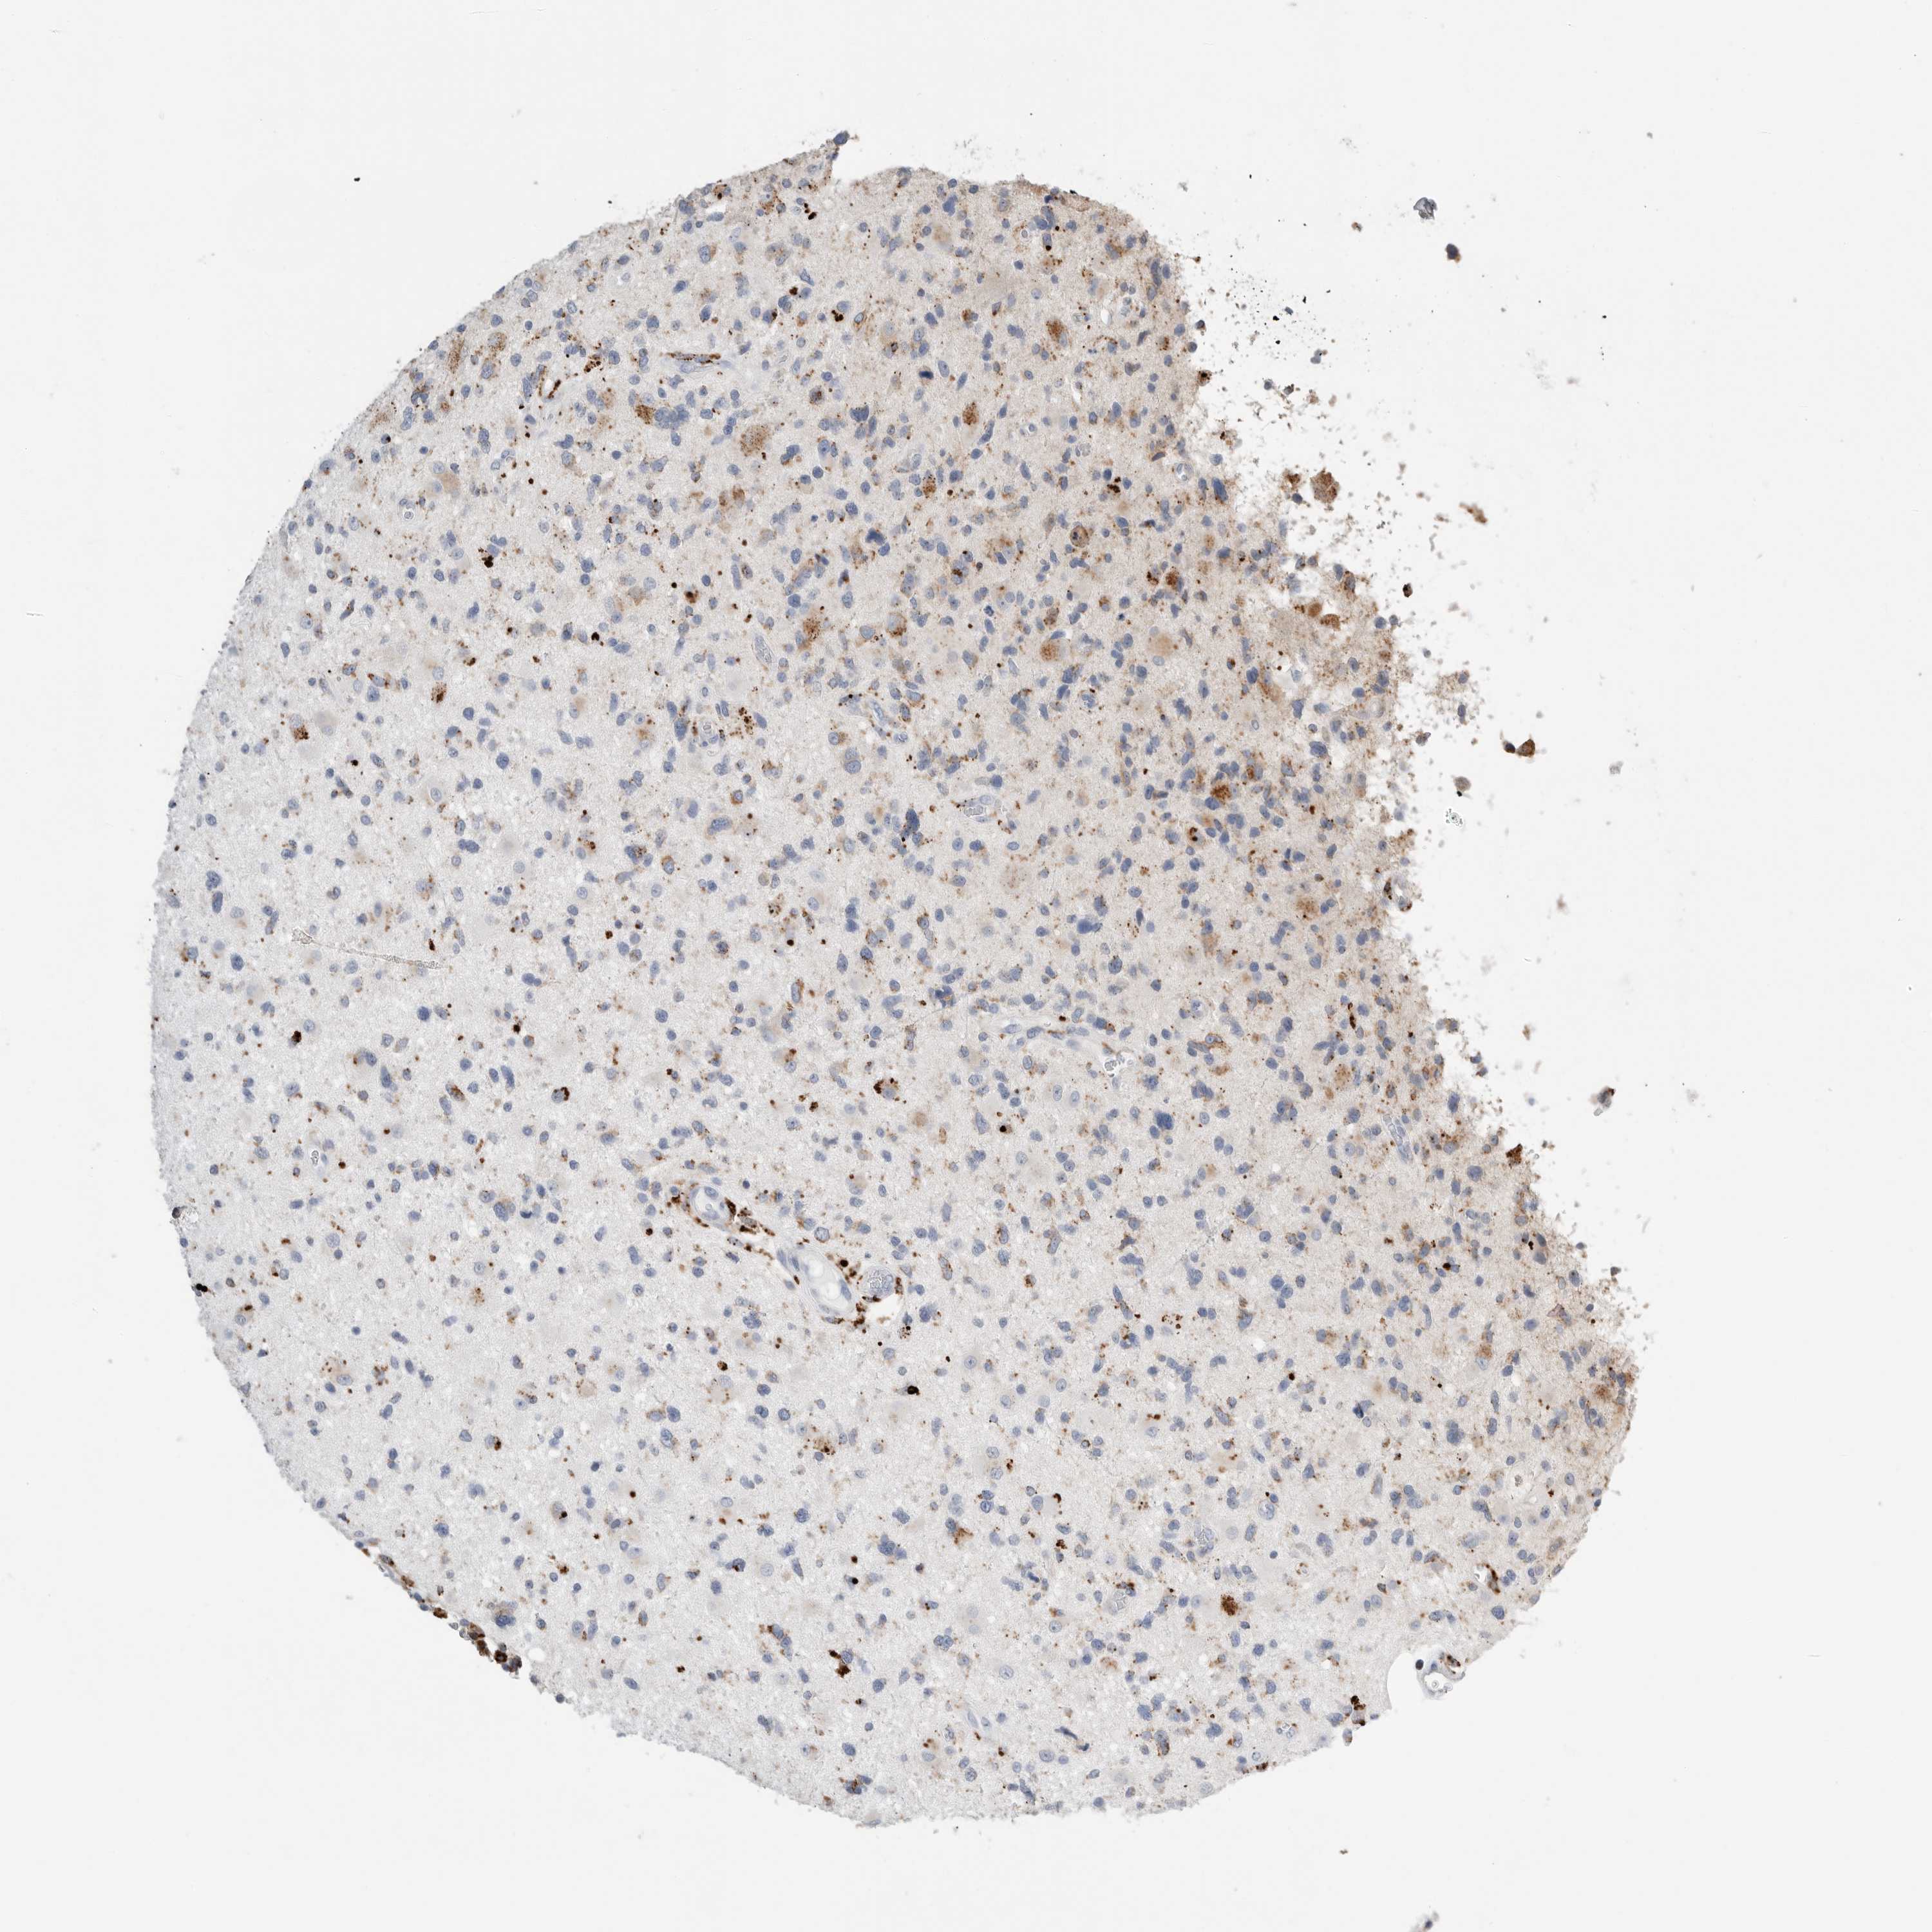

GLIOMA - Protein expressioni

A mouse-over function shows sample information and annotation data. Click on an image to view it in a full screen mode. Samples can be filtered based on level of antibody staining by selecting one or several of the following categories: high, medium, low and not detected. The assay and annotation is described here.

Note that samples used for immunohistochemistry by the Human Protein Atlas do not correspond to samples in the TCGA dataset.

Antibody stainingi

Antibody staining in the annotated cell types in the current human tissue is reported as not detected, low, medium, or high, based on conventional immunohistochemistry profiling in selected tissues. This score is based on the combination of the staining intensity and fraction of stained cells.

Each image is clickable and will lead to virtual microscopy that enables deeper exploration of all samples and also displays staining intensity scores, fraction scores and subcellular localization as well as patient and tissue information for each sample.

Antibody HPA025226

Antibody CAB019296

Staining

High

Medium

Low

Not detected

Intensity

Strong

Moderate

Weak

Negative

Quantity

>75%

75%-25%

<25%

None

Location

Nuclear

Cytoplasmic/membranous

Cytoplasmic/membranous,nuclear

Glioma, malignant, High grade

Glioma, malignant, Low grade